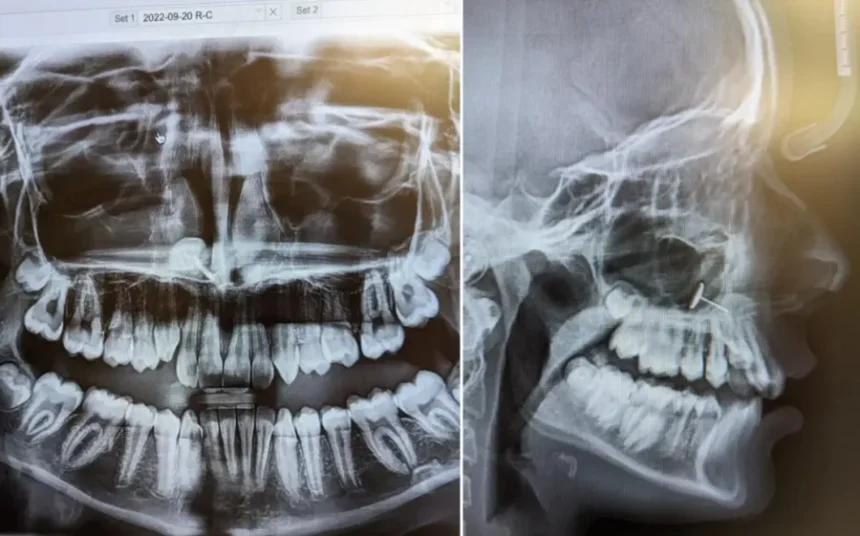

Сликата покажала мал метален предмет заробен во синусите на нејзината ќерка. Мајката немала поим како можел да стигне таму, но едно лице во собата точно знаело што се случило: нејзината ќерка.

„Ја зеде обетката што беше во ушите и се обиде да ја турне во носот“, објасни мајката. „Очигледно во еден момент се обидела да ја турне обетката во носот одвнатре“, рече мајката на тинејџерката. „Не знам дали кивнала, но на крајот ја вдишала обетката. Се заглавила во синусите.“

„Откако сфативме што е тоа и како стигнало таму, го повикав специјалистот за уво, нос и грло кој ѝ ги отстранил крајниците пред години, и со многу долг медицински форцепс и стабилна рака, тој го отстрани предметот. Мојата ќерка не почувствува болка за време на постапката и, со оглед на околностите, го толерираше доста добро“, заклучи олесната мајка за Newsweek.